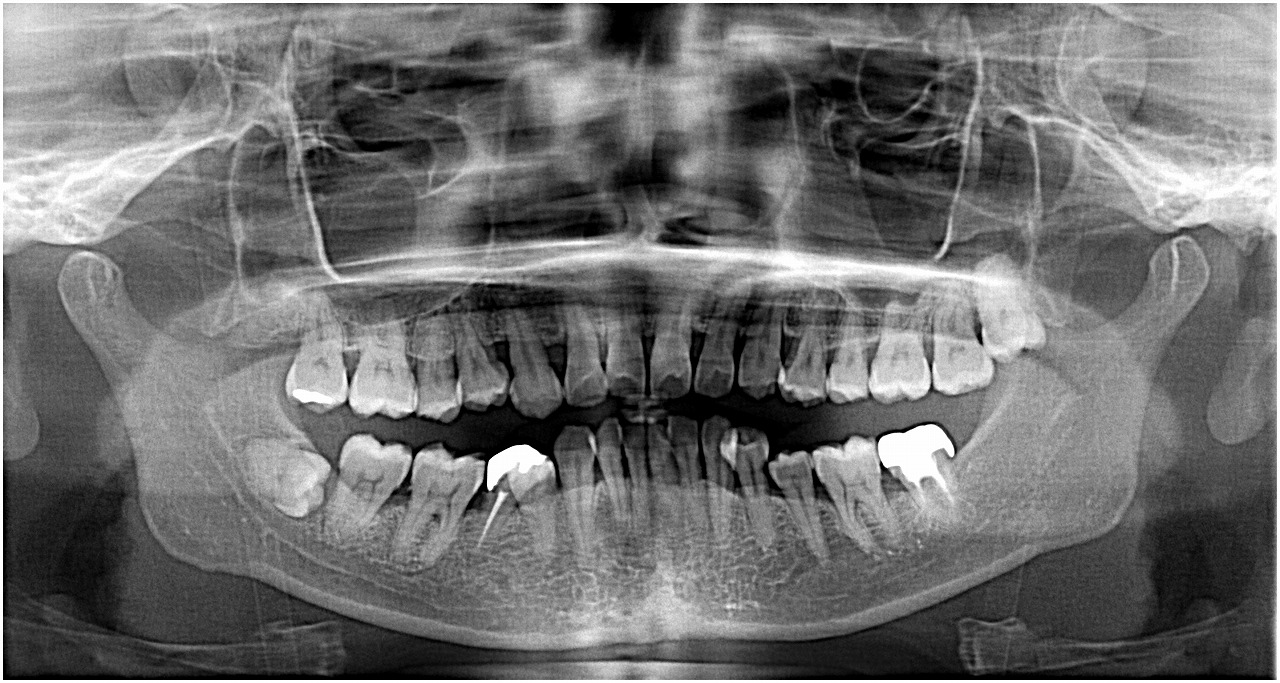

お知らせ|広島市安佐南区の歯科医院 > お知らせ トップ お知らせ・ブログ お知らせ スタッフブログ お知らせ お知らせ 2021/06/02 前歯にブリッジをしているのですが、、、 歯茎が腫れだして痛むとのこと お知らせ 2021/06/01 左上7番の術前CTデータからこの歯は歯周病も進み保存不能と判断しました お知らせ 2021/06/01 左上の奥が硬いものを噛むと痛む診てほしい 時々腫れては引いてを繰り返してきた 手で触っても歯が動くように感じる お知らせ 2021/05/31 左上1番欠損の審美的なブリッジを入れていきます お知らせ 2021/05/31 ジルコニアによるラミネートベニヤの症例 昔から歯の間に徐々に隙間が空いてきて気になっていた 何とかしてほしい お知らせ 2021/05/29 右下の奥歯の親不知を抜きたい診てほしい 昔から腫れたりを繰り返してきたが、、そこの歯医者では抜けないといわれてきたのでそのままにしてきた お知らせ 2021/05/29 左上の前歯を1時間前に打った 歯が折れたので診てほしい お知らせ 2021/05/28 前歯を打って歯が折れた 診てほしい お知らせ 2021/05/28 右上の完全埋伏歯の難抜歯 全く生えていない歯ですが、、 他医院にて親知らずを指摘されてそこでは抜けないと 矯正をしたから抜歯しときたいとのこと お知らせ 2021/05/27 口唇をよく噛んでいたら腫瘍ができた さらに噛むようになったので診てほしい << 1 2 3 4 5 … 210 211 212 213 214 … 485 486 487 488 489 >> Web診療予約 初めての方へ 選ばれ続ける理由 院内設備について 歯が痛いしみる一般歯科 歯がぐらぐらする歯周病 健康な歯を保ちたい予防歯科 子供の虫歯予防をしたい小児歯科 銀歯をセラミックに審美歯科 白い歯を目指しませんか?ホワイトニング 矯正専門医がいるので安心矯正歯科 抜けた歯を補いたいインプラント・入れ歯 医院案内 スタッフ紹介 メリィハウス歯科クリニックオフィシャルホームページ ラベンダー歯科クリニックオフィシャルホームページ お知らせ・ブログ ホーム 診療科目 一般歯科 歯周病治療 予防治療 小児歯科 審美治療 ホワイトニング 矯正歯科 入れ歯・インプラント マウスピース矯正 初めての方へ 院長・スタッフ 設備紹介 医院案内・アクセス メニューを閉じる